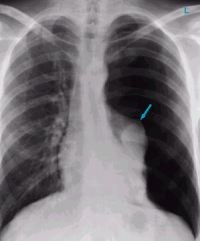

Задание   №  17 .

Перед  Вами-   рентгеновский   снимок  грудной    клетки .

есть  ли   травма?

Предположите   Диагноз .

Ответ   25.02.25    после   17.00.по  мскв .

Травма есть , но перелома не ощущается. затемнение части легкого , как ощущение некоего обьема , и плотности тканей , кровоизлияние . Опухоль тоже возможна .

Ответ  на   задание   №  17 .

Ответ: травмы нет,но есть некое застойное явление. вот  тут  близко:   коллабированое   ,  "поджатое"  легкое.  Это позвоночный столб.

22.02.2026 в 12:28, Sowa сказал:

Отличный   просмотр,    объем- Воздух) 🌹

Но дышится немного больно, как будто ушиб или бронхит.  оч  близко,  симптоматика   при   пневмотораксе-  и  боль   при  дыхании,  и  одышка.🌺

Скрытый текст

Пневмоторакс —скопление воздуха в плевральной полости. Это приводит к сдавливанию лёгкого, из-за чего оно не может полностью расправиться при вдохе. В результате нарушается дыхание, а в тяжёлых случаях может возникнуть угроза для жизни.

стрелочкой   указано  коллабированое ( поджатое) легкое  на    стороне  поражения.